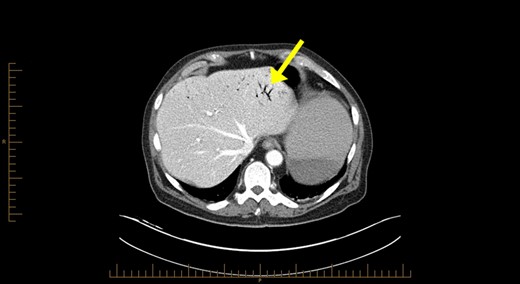

Blood investigations revealed a low haemoglobin of 104 g/l (115–165 g/l), low white cell count 1.56 × 109/l (4.0–10.0 × 109/l) with normal coagulation, liver function, lipase and lactate parameters. Competent tomography (CT) abdomen scan identified grossly thickened small bowel with a large amount of portal venous gas in liver (Figs 1 and 2). Like us, the radiologist was concerned these features were highly suggestive of small bowel ischaemia.

Computerized tomography abdominal axial section showing air within the hepatic portal veins (yellow arrows).

The pathophysiology of HPVG is unclear, but two hypotheses in the literature exist. The first states that factors such as mucosal barrier damage, bowel distension, increased intraluminal pressure and bacterial fermentation of carbohydrates in sepsis result in gas production [5]. The second theory is that gas-forming organisms present in the intestinal wall or venous system causes HPVG [5]. As seen in Fig. 1, HPVG is characteristically distributed as peripheral radiolucencies extending to within 2 cm of the liver capsule.